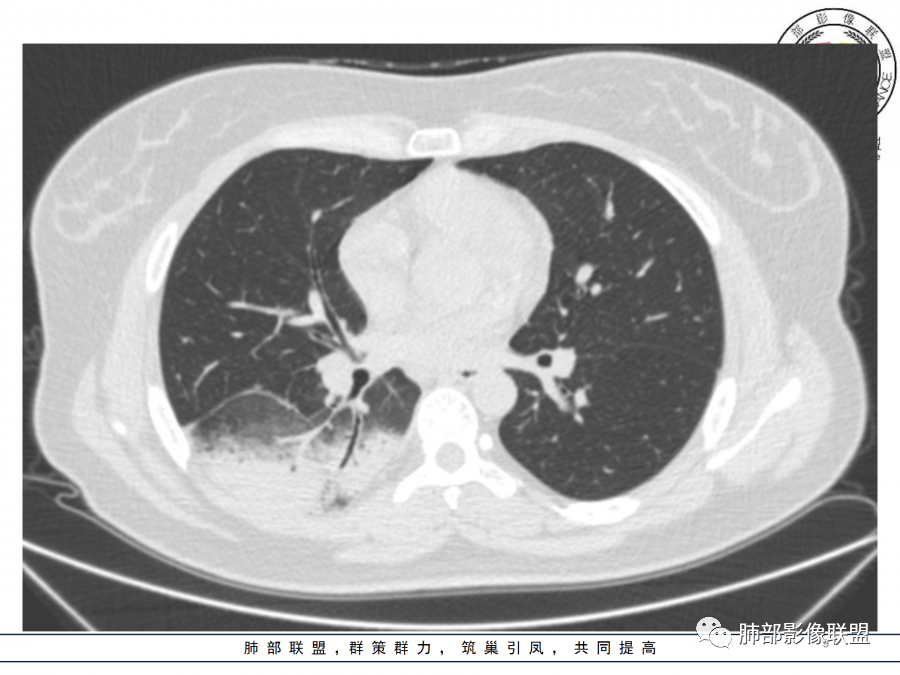

右肺胸膜下实变,病变跨多个叶生长,宽基底与胸膜相连,近端支气管穿行病灶内,并可见片状磨玻璃影,边界清,部分远端小支气管堵塞,支气管略有扩张,周围散发小结节,临床年轻女性,炎性指标高,发热六日,首先考虑感染性病变(肺链,奴卡,隐球,OP)鉴别淋巴瘤。

青年女性,发热咳嗽5天,炎症标志物升高。右肺下叶大片实变伴周围GGO,GGO内未见细网格,主体与胸膜平行,似多个病灶融合,实变区内见支气管部分进入,部分支气管受压狭窄,周围可见多发卫星病灶。支持炎性,考虑隐球感染,鉴别op。

年轻女性,急性起病,咳嗽,发热,黄痰,白细胞高,CRP基本正常,基础体健。CT提示右肺下叶实变,宽基底与胸膜相连,长轴平行于胸膜,可见支气管充气征,于病变中央截断,走形自然,胸膜下脂肪间隙可见,倾向于隐球菌,鉴别肺链,军团菌等。

26岁,女性,发热、咳嗽5天。咳少量黄痰,起病急,病程短,白细胞及中性高,血沉及D-二聚体增高。胸部CT:右肺下叶大片实变,长轴沿胸膜分布,宽基底与胸膜接触,边界不清,周围GGO,部分团片影融合,病灶内可见支气管充气征,部分支气管进入病灶后阻塞。考虑:感染性病变,隐球菌?脓毒肺栓塞?鉴别:肺炎型肺Ca。

细菌性肺炎是沿着支气管往周围肺泡散开,内朝外,沿着叶段分布,受到支气管管辖,呈扇形,与支气管长轴平行,与胸膜垂直,隐球菌就是外朝内,外就是肺小叶内的肺泡,外周的。

肺小叶。他就是一个个肺小叶的融合,胸膜平行,和病毒一样。只是病毒在间质,是肺小叶分布的毛玻璃。隐球菌是肺实质,肺泡,肺小叶的实变。

这个病变也不是一个起源中心,胸膜下,多发结节状、实变影。而大叶性肺炎多数由内-外大片状。所以是肺实质多发融合病变。单纯从影像上,还是比较符合隐球菌特点,胸膜下,多发、多中心,相互融合(兄弟齐心)。